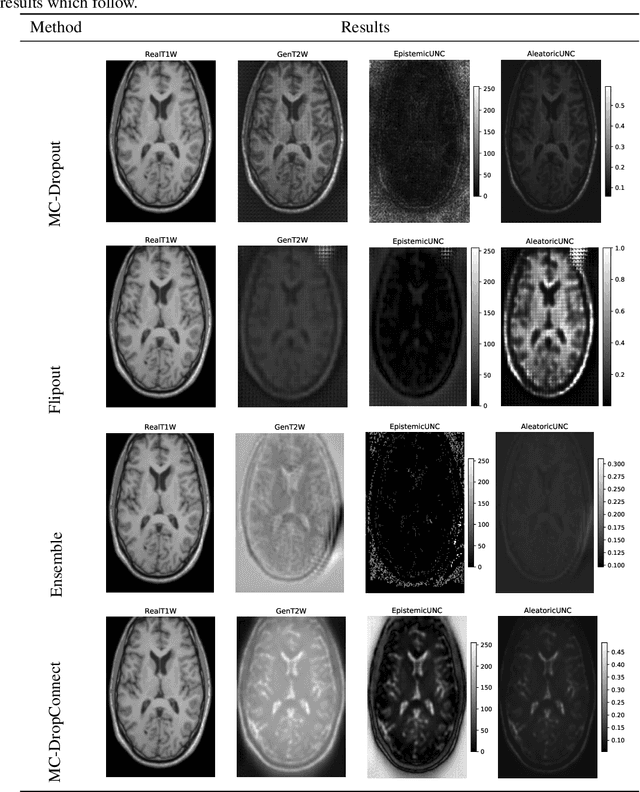

Abstract:Trusting the predictions of deep learning models in safety critical settings such as the medical domain is still not a viable option. Distentangled uncertainty quantification in the field of medical imaging has received little attention. In this paper, we study disentangled uncertainties in image to image translation tasks in the medical domain. We compare multiple uncertainty quantification methods, namely Ensembles, Flipout, Dropout, and DropConnect, while using CycleGAN to convert T1-weighted brain MRI scans to T2-weighted brain MRI scans. We further evaluate uncertainty behavior in the presence of out of distribution data (Brain CT and RGB Face Images), showing that epistemic uncertainty can be used to detect out of distribution inputs, which should increase reliability of model outputs.